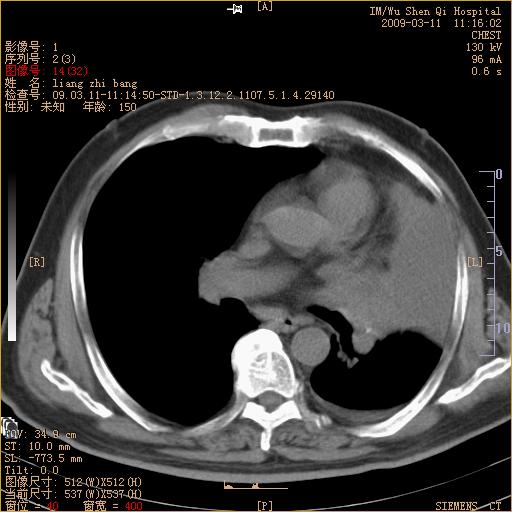

标题: CT18604:男,60岁,咳嗽一月余 [打印本页]

标题: CT18604:男,60岁,咳嗽一月余

1)考虑左肺上叶中央型肺癌并左肺上叶肺不张;建议必要时行纤支镜检查进一步明确诊断。2)左侧胸腔积液。

肺门肿块、支气管开口闭塞伴肺不张及胸水!典型的中心型肺癌变现!

1、左肺上叶中央型肺癌并上叶阻塞性肺不张。

2、左侧胸腔少量积液,右侧胸膜轻度增厚。

左肺们肿块并左肺上叶不张。考虑左肺中心性肺癌并左肺上叶不张及左侧胸腔积液